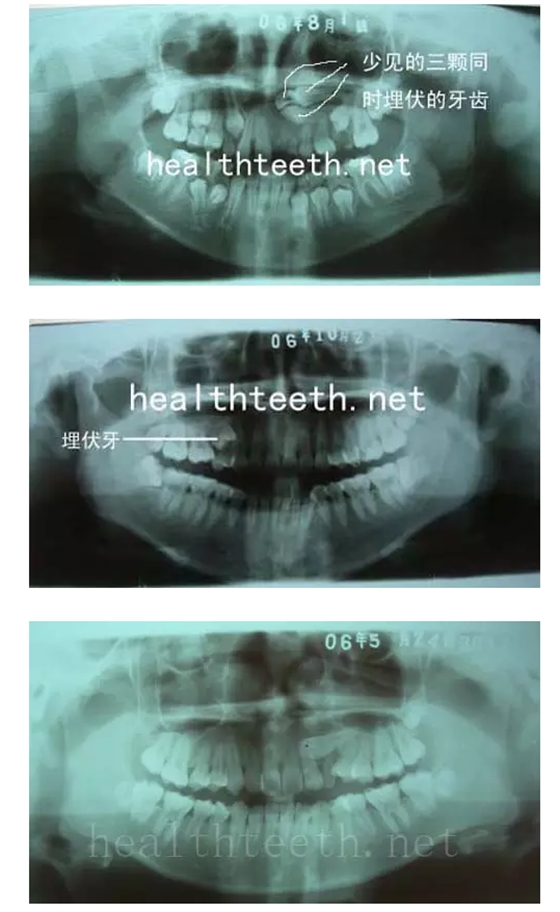

2、埋伏牙

左上乳3滯留,恒3未見萌出,曲面斷層片顯示牙齒埋伏

QQ圖片20150722094029.png

通過CT片確定埋伏牙齒具體的位置,顯示距離左側上頜竇很近,偏唇側,這為手術定位提供了方便

QQ圖片20150722094055.png

QQ圖片20150722094148.png

QQ圖片20150722094204.png

手術中切斷、完整拔出,未損傷上頜竇

QQ圖片20150722094218.png

其他埋伏牙

QQ圖片20150722094235.png

QQ圖片20150722094247.png